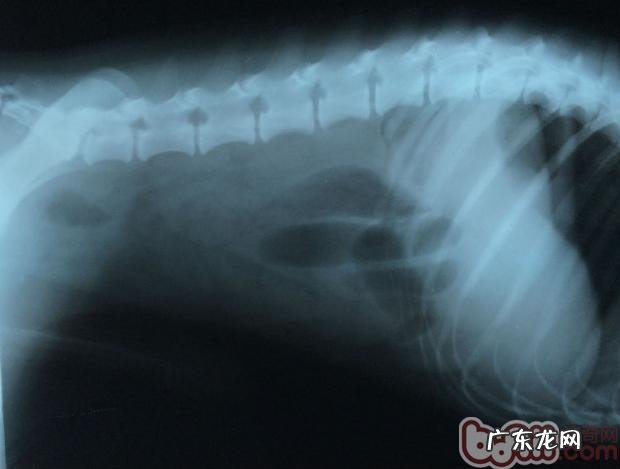

X线显示信息:在乙状结肠位置有一硬块 , 箭头符号所说 , 堵塞物前有汽体无法排出来 。